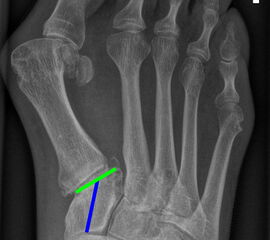

Gelenkflächenwinkel

DMAA (Distal metatarsal artikular angle, Syn. Gelenkflächenwinkel): Winkel zwischen der Achse des Os metatarsale I (rot) und dem Lot auf die distale Gelenkflächenebene (blau) des Os metatarsale I. Die Gelenkflächenebene (grün) wird definiert durch zwei Punkte, welche die mediale und laterale Begrenzung der Gelenkfläche definieren (Norm: <10° 5). Die Projektion des DMAA ist stark abhängig von der Rotation des Os metatarsale I 7. Daher ist bei der operativen Behandlung des Hallux valgus eine Beurteilung häufig erst nach Korrektur der Pronationsstellung des Os metatarsale I möglich. Tendenziell wird der DMAA auf präoperativen Röntgenaufnahmen überschätzt.

TMT-1-Gelenk dorsoplantar (Tarsometatarsale-1-Gelenk)

In der dorsoplantaren Aufnahme kann ein Versatz der Gelenkfläche im TMT-1 Gelenk auf eine Instabilität hindeuten. Phasenweise wurde auch die Ausrichtung der distalen Gelenkfläche des Os cuneiforme I (grün) zur Achse des Os cuneiforme I (blau) als Risikofaktor diskutiert, hat sich aber aufgrund der starken Projektionsabhängigkeit nicht bewährt 10. (Norm 0-15° 9).